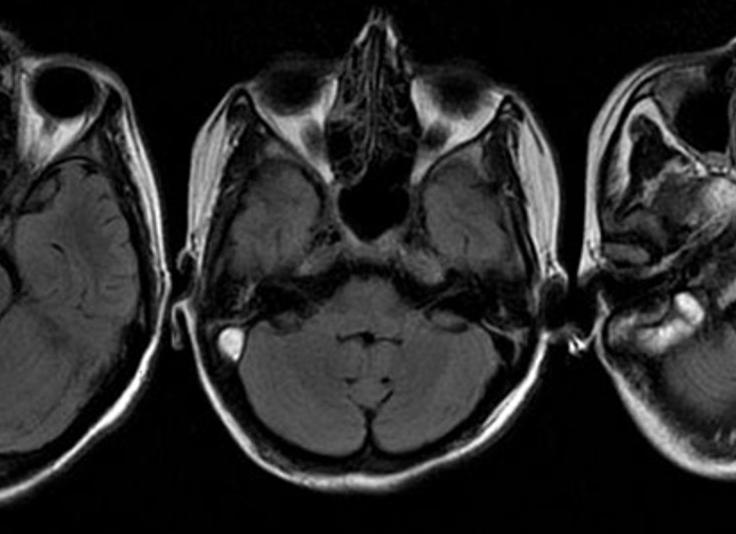

МРТ головного мозга при субдуральном абсцессе (после контрастирования) с поражением лобных пазух